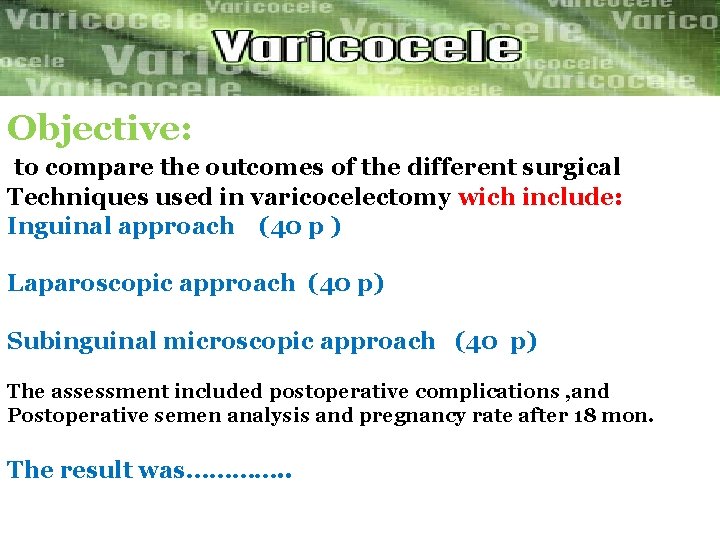

Objective: to compare the outcomes of the different surgical Techniques used in varicocelectomy wich include: Inguinal approach (40 p ) Laparoscopic approach (40 p) Subinguinal microscopic approach (40 p) The assessment included postoperative complications , and Postoperative semen analysis and pregnancy rate after 18 mon. The result was…………. .

Conclusions The findings of our study have demonstrated That , compared with open inguinal , laparoscopic, and microscopic Sub inguinal microsurgical varicocelectomy offers The best outcomes.